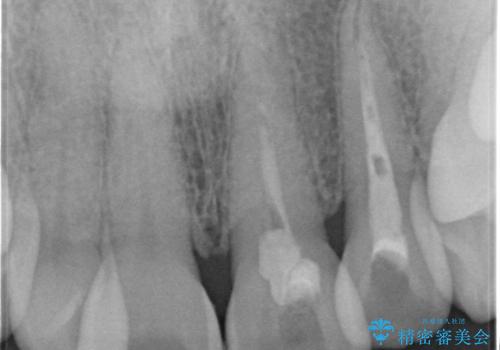

- 前歯の変色を主訴に来院された患者様です。

再根管治療からのやり直しも提案しましたが、特にご希望されなかったためクラウンでの修復処置のみ行います。

歯は根管治療が終了して時間が経つとだんだん茶色く変色していきます。